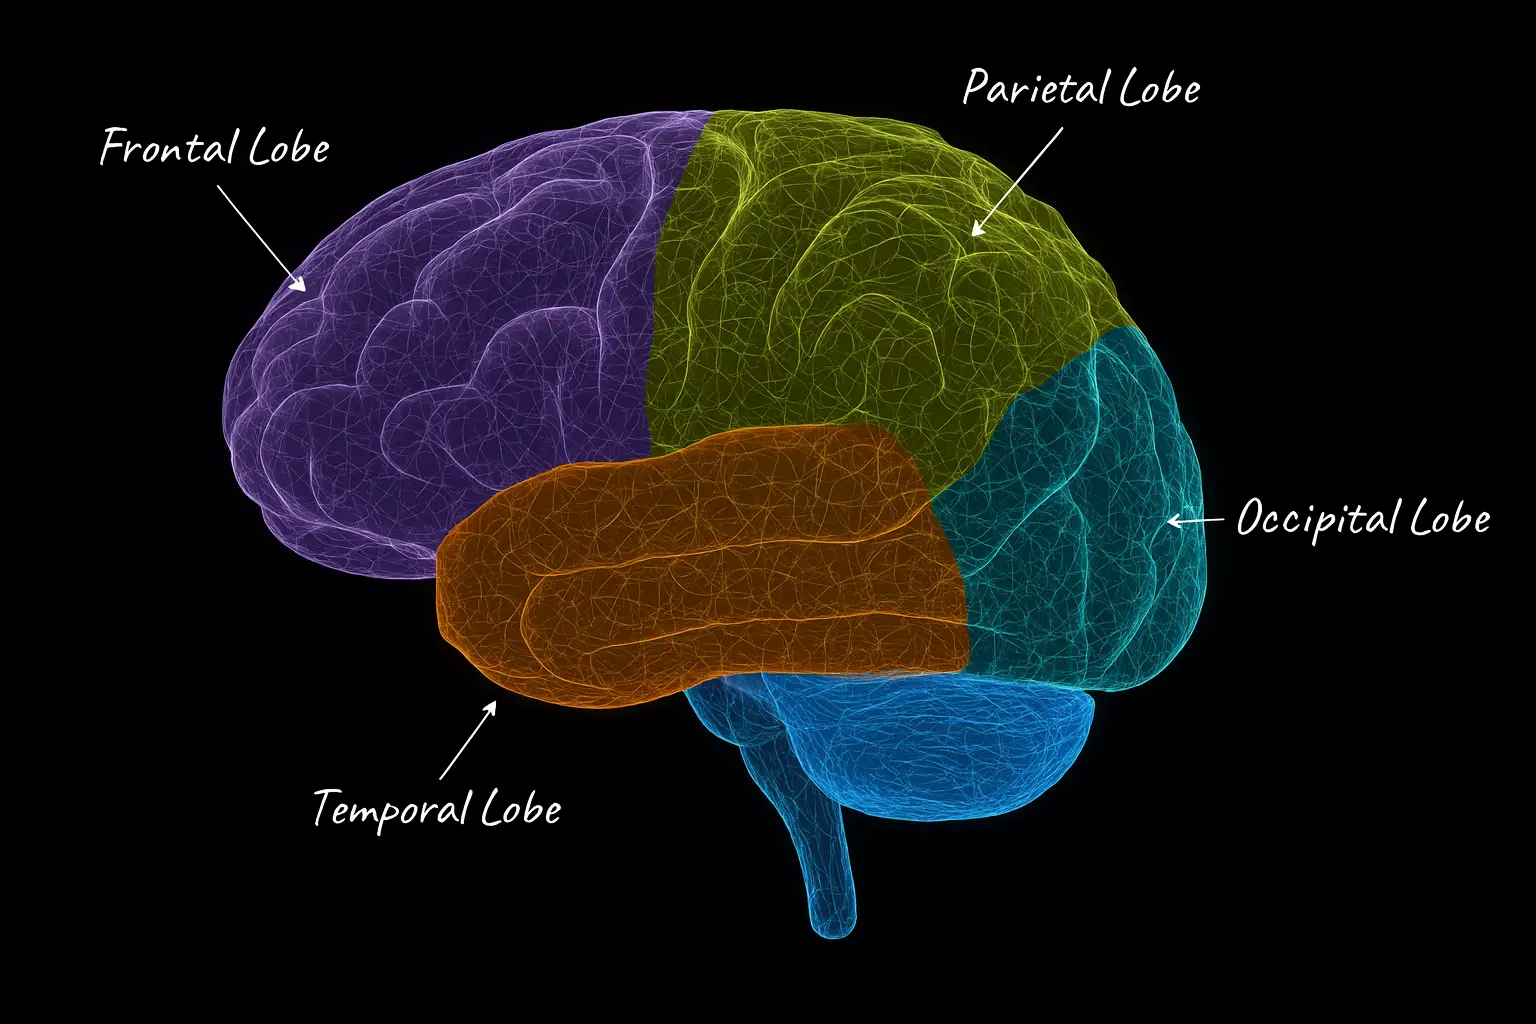

Frontal-Parietal-Temporal Lobe Structure & Function - Fast Track

This 25-hour advanced module explores the root causes and clinical applications for neuroinflammation and neurodegeneration. Learn how to assess and manage conditions like Alzheimer’s, Parkinson’s, and TBI using tools grounded in neuroscience.